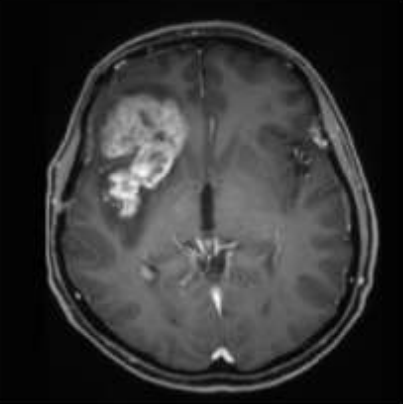

膠質(zhì)瘤復(fù)發(fā)診斷:是惡性進(jìn)展還是放射性壞死?

然而,在某些情況下,可能需要注意細(xì)微的差異:更球形、界限更清晰的形狀可能提示膿腫而不是復(fù)發(fā)性惡性膠質(zhì)瘤;周圍水腫的彌漫性、不規(guī)則邊緣模式可能提示放射性壞死而不是復(fù)...